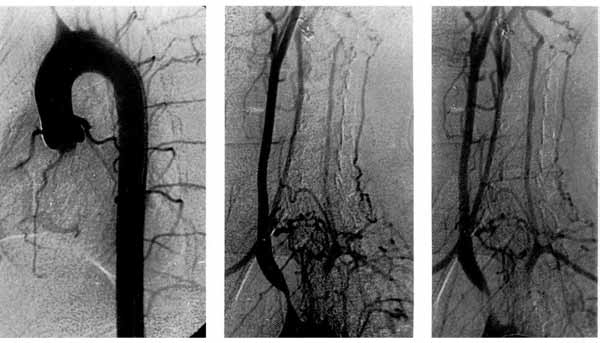

MSCT – precizna analizua  morfologije lezija  supraaortalnih arterija

Tipične glatke stenoze

dugih segmenata svih

supraaortalnih grana

(»znak makarona«).

Leva karotidna arterija

se puni retrogradno.